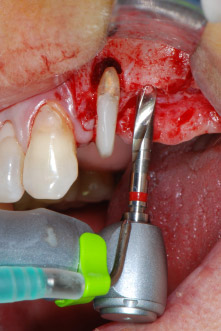

Les lits implantaires ont été préparés sur les sites 25 et 26 à l'aide d'instruments rotatifs, utilisés dans un contre-angle avec un rapport de transmission 20:1 avec un nouveau moteur d'implantologie puissant (Implantmed, W&H) (Fig. 8).

La préparation finale près du sinus a encore une fois été réalisée à l'aide d'un instrument piézoélectrique (Piezomed, insert S2).